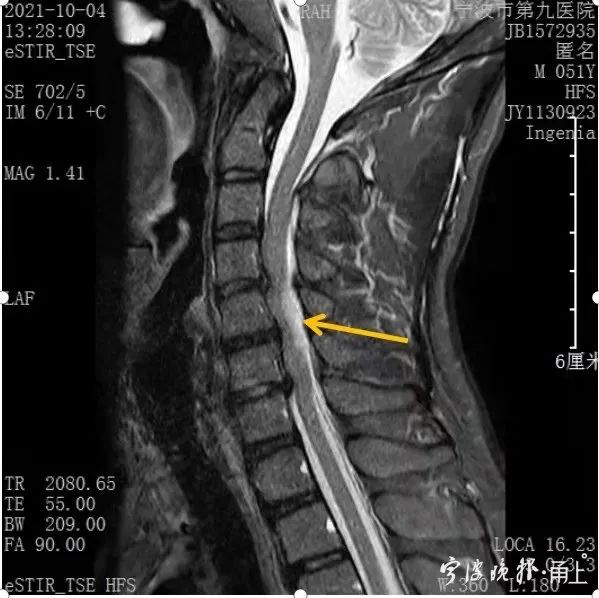

徐醫生當時就懷疑是脊髓出血。頸椎處的脊髓出血,壓迫到脊神經,就會引起高位截癱,從而導致感覺和知覺障礙。

經過對患者頸椎磁共振檢查和骨科專家會診,確診為無骨折脫位性的頸脊髓損傷,又叫甩鞭樣損傷。